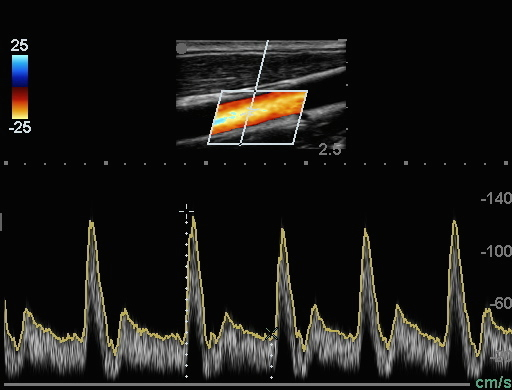

Bild 2: Karotis – Doppler-Kurve